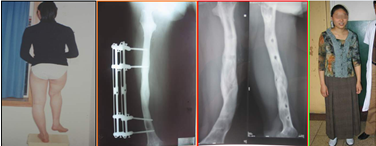

病例3:患者,男,16岁,股骨外髁不发育导致K型腿并短缩11公分。行外固定支架截骨矫形,延长11cm,骨痂生长良好。

病例4:先天侏儒畸形,双胫骨仅17CM,身高128CM,伴“O”形腿。术后情况:纠正O型腿并延长14cm。